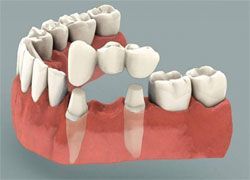

Адгезивное протезирование: мостовые протезы в клинике «Интердентос»

Современное протезирование зубов в стоматологии позволяет добиваться полного восстановления зубного ряда, его эстетичности и функциональности.